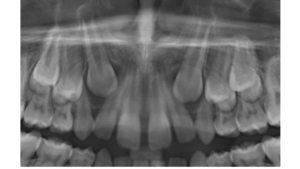

Aspecto radiográfico da fase do patinho feio com o pressionamento dos caninos sobre as raízes dos incisivos laterais

Naturalmente os caninos utilizam as superfícies distais das raízes dos incisivos laterais como guia de erupção. Esse fato desencadeia eventos característicos de uma fase de transição dos dentes decíduos para os permanentes (fase do patinho feio). A pressão intraóssea dos caninos, sobre a superfície distal das raízes dos laterais provoca um deslocamento das raízes desses dentes em direção à linha média, convergindo-as e, consequentemente, divergindo as suas coroas. Nessa fase, os espaços entre as coroas e as inclinações dos incisivos superiores serão frequentes e esperados. Contudo, devemos ficar atentos aos movimentos dos caninos. A visualização, na radiografia panorâmica, de uma sobreposição da imagem da coroa do canino em relação à raiz do incisivo lateral e a angulação com que isso ocorre torna-se preocupante. Muitas vezes esses caninos deslocados terão de ser tracionados ortodonticamente para a sua posição no arco dentário.